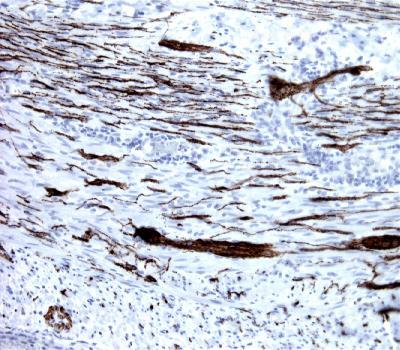

Figure-1: Appendix section has been stained using Synaptophysin antibody (Clone: BS15) with 1:300 dilution. Ganglion cells and neuronal axons stained strongly.